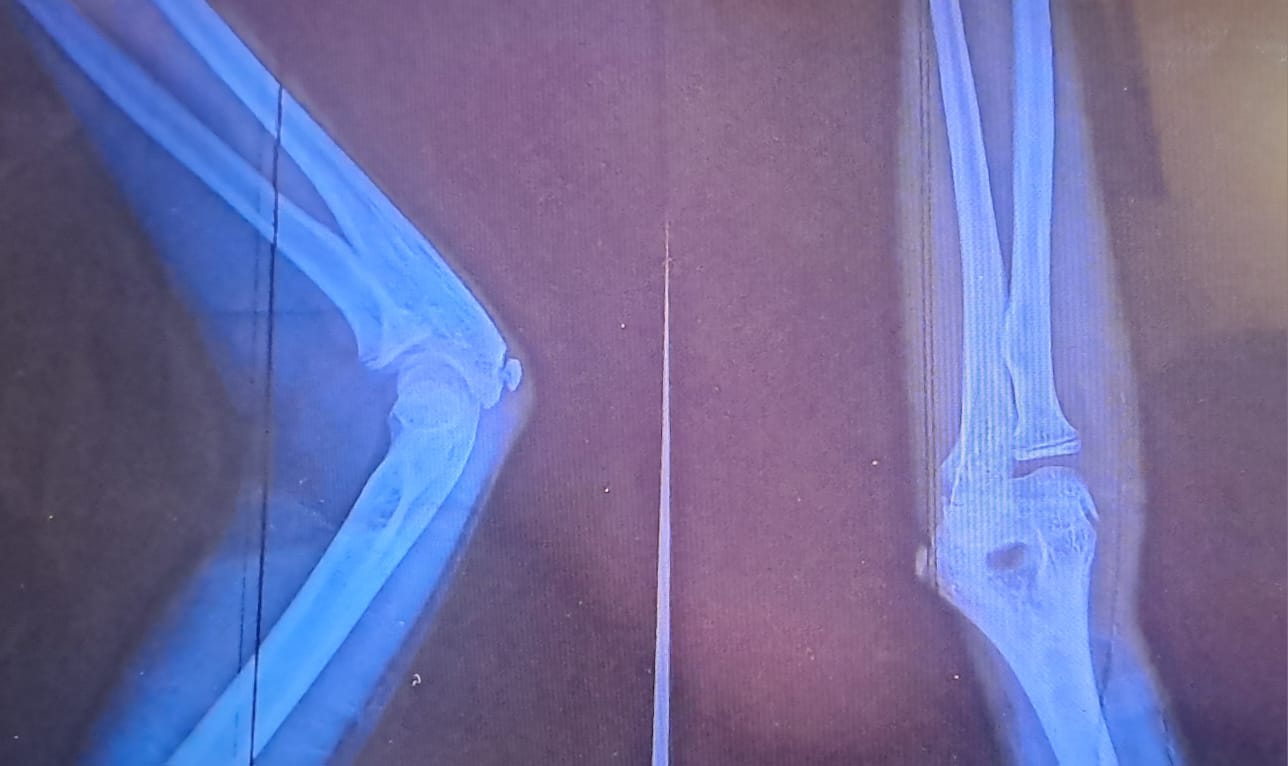

दैलेख – ज्ञान, चेतना, शिक्षासंगै विद्यालयमा रहुञ्जेल सुरक्षा दिने ठाउँ पनि हो विद्यालय । तर दैलेख सदरमुकामको त्रिभुवन मावि दैलेखबजारमा शिक्षकको कुटाईबाट एक जना बालिका घाइते भएकी छिन् । त्यहाँका शिक्षक गणेश रेग्मीले लाठीले हान्दा कक्षा ६ की ११ वर्षीया छात्रा महालक्ष्मी न्यौपानेको दाहिने हातकाे कुहिनाकाे हड्डी चर्केको छ ।

गत बुधबार दिउँसो कक्षा ८ र ९ को ग्याङ फाइट भएको बेला रम्चारुलाई धपाउदै गरेको बेला ती शिक्षकले लाठीले जोडसंग हानेको कारण दाहिने हातकाे कुहिना हड्डी चर्केकाे लेखपढ गर्न समेत वाधा परेकाे बालिका महालक्ष्मी न्यौपानेले बताउनुभयो । शिक्षक रेग्मीले भन्नुभयो ‘धपाएको हाे तर हानेकै त मलाई लाग्दैन, तर हुलभीडकाे सबै याद छैन ।’

‘बोर्डिङमा पढिरहेकी छोरीलाई सरकारी विद्यालयमा नाम लेखाइयो तर शिक्षकले कुटपिट गरेर अपाङ्ग बनाएकोमा दुख लागेको छ’ बालिकाकी आमा शान्ति न्यौपानेले असन्तोष व्यक्त गर्नुभयो । लेख्ने गरेको दाहिने हातमा चोट लागेकाे कारण आफूलाई लेख्न साह्रै कठिनाई भइरहेकाे घाइते बालिका महालक्ष्मीले पहरेदारलाई बताउनुभयो ।